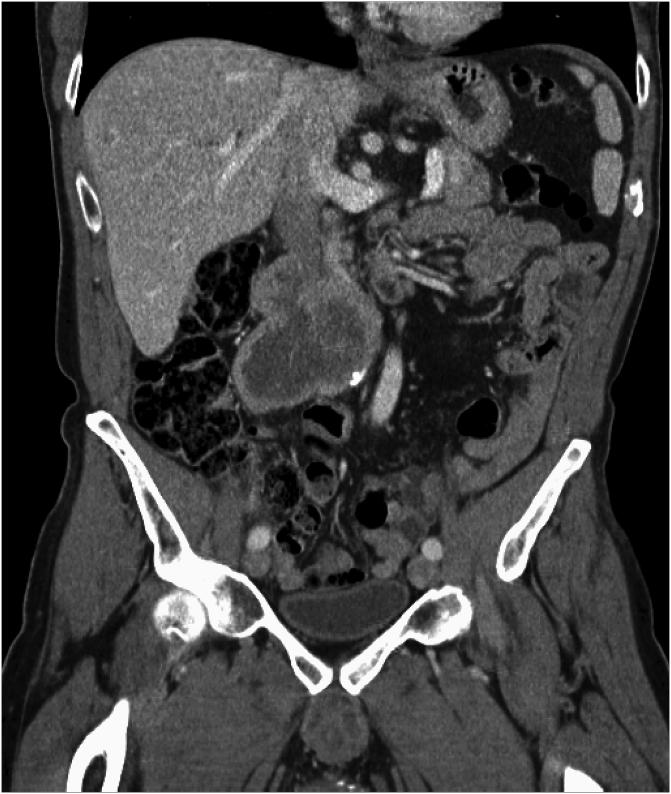

Primary angiosarcoma of the testis with retroperitoneal metastasis.

Urol Case Rep. 2018 Sep 19;21:116-118. doi: 10.1016/j.eucr.2018.09.014. eCollection 2018 Nov.